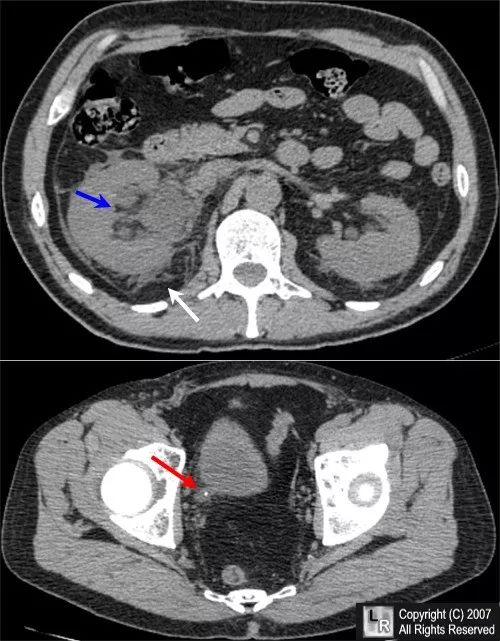

CT图像上可发现输尿管膀胱连接部水肿、肾周积液、肾脏增大等表现(图1)。

图1 输尿管结石阻塞。下腹部CT显示右肾增大伴肾周脂肪绞合(白色箭头),肾内集合系统扩张(蓝色箭头),输尿管膀胱交界处钙化灶(红色箭头),伴输尿管扩张